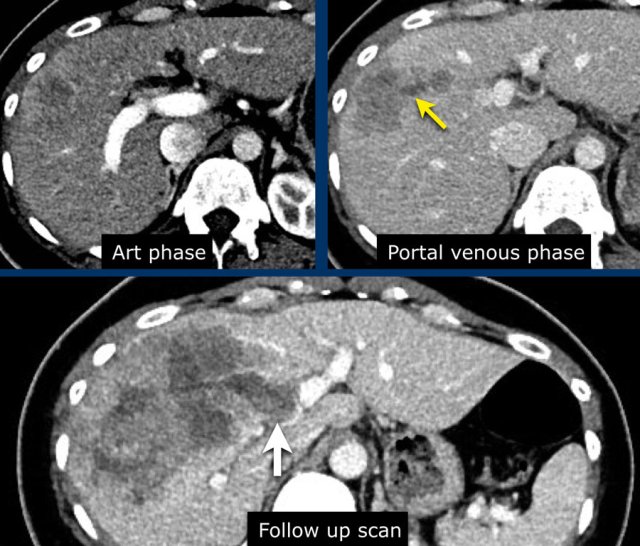

Arterial, PV and delayed phase images of a LIRADS 3 observation.

In segment 5 there is a subcapsular observation of intense arterial enhancement without washout in the PV or delayed phase.